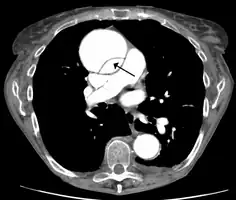

-

Aortic dissection -

CT with contrast demonstrating aneurysmal dilation and a dissection of the ascending aorta (type A Stanford) -

Chest CT with descending (type B Stanford) aortic dissection (red circle)

Type A dissection with pericardial effusion as a result.